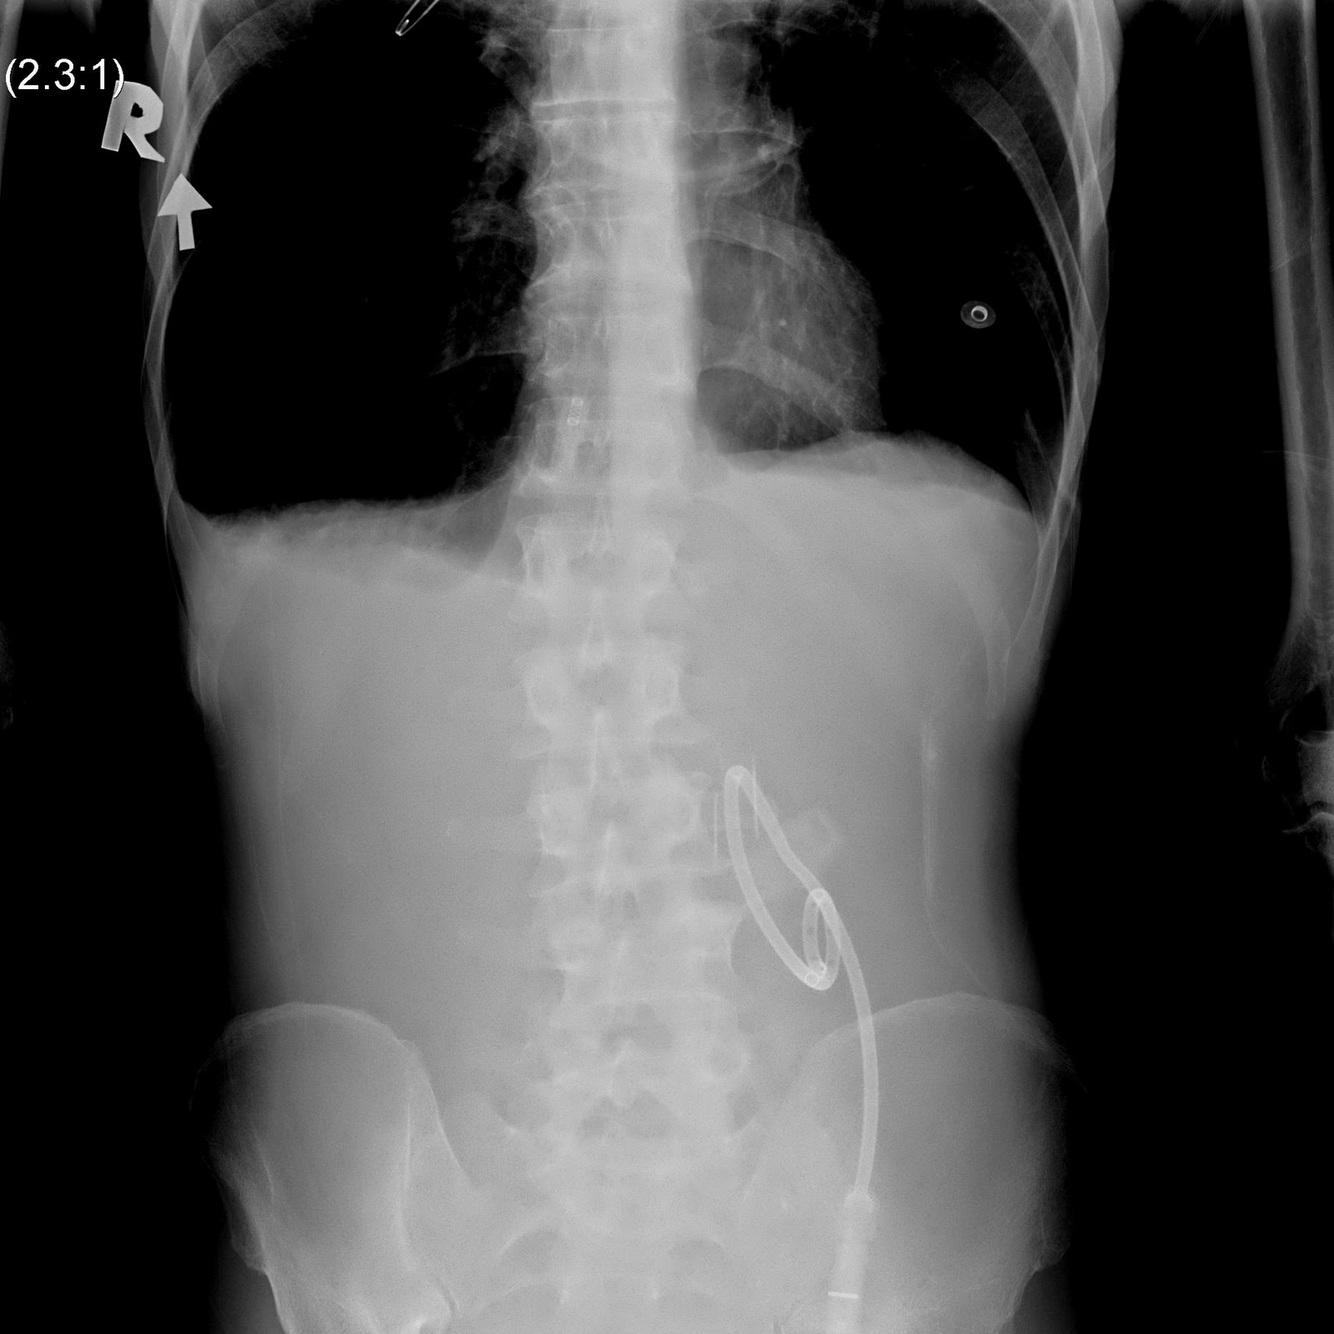

What is the DDx for a Gasless Abdomen?

Gasless Abdomen DDx

Adults:

Child: